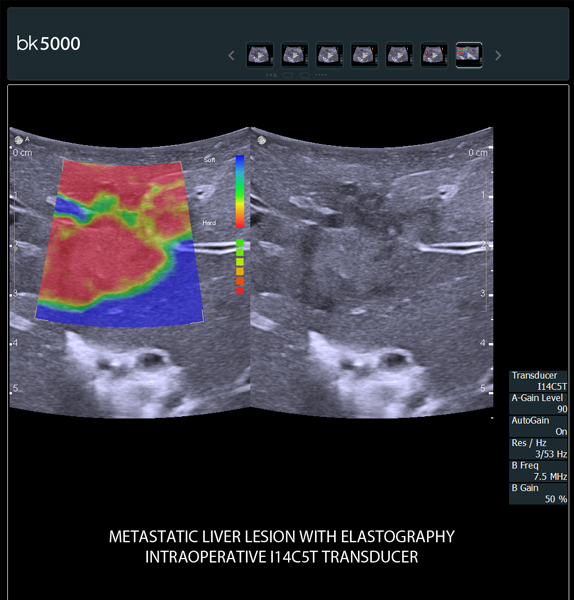

Ultrasound can advance intraoperative surgical procedures by helping you navigate and identify lesions and anatomical structures in real-time. This is particularly important as the data obtained from a preoperative CT or MRI scan can be outdated at the time of surgery.

The bk5000 surgical system provides the highest quality images that allow you to clearly see the margins of a lesion and to determine the best course of action. Using advanced graphics processing technology, this powerful system provides immediate, auto-optimized images that allow you to see the information you need, faster.